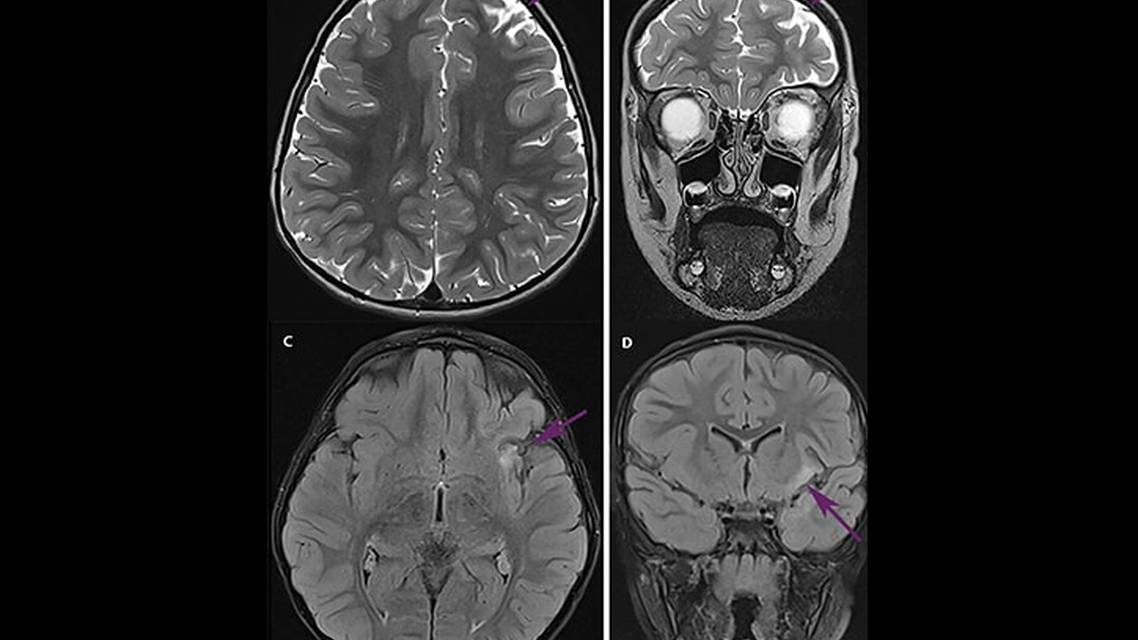

EEG most commonly shows unilateral hemispheric polymorphic delta waves, intermittent focal slowing, and multifocal ictal and interictal discharges.13-15 Clinical and subclinical seizures occur.11 Although it is atypical, there have been reports of ESES in Rasmussen encephalitis.16 Imaging is typically notable for unilateral focal atrophy, most commonly involving the insular cortex, associated with ipsilateral ventricular enlargement.13,15 There is also associated cortical and subcortical white matter T2 and FLAIR signal changes, usually surrounding the areas of cortical atrophy.15 Histopathology should provide evidence of a chronic inflammation including T-cell dominated encephalitis with activated microglia, and parenchymal macrophages.13,14

AJ met the proposed criteria with clinical assessment, EEG, and MRI findings. He did not develop several of the classic symptoms, however, including progressive cerebral atrophy, EPC, or hemiparesis and quickly transitioned from a prodromal to acute phase. Although AJ initially had a tonic-clonic seizure, within a couple of months he was having multiple seizure types as he progressed to the acute phase. His seizures were resistant to 3 adequately trialed ASMs without success. AJ’s EEG findings were consistent with a focal process, exhibiting focal slowing in the left temporal region and evidence of a focal seizure, although he also developed focal ESES, which is not commonly seen with Rasmussen encephalitis. His stereoEEG was notable for multifocal seizures and discharges. Throughout his 6-month workup he had 3 brain MRI’s that did not show any interval change but consistently showed signal abnormalities in the left anterior insula, left caudate, and frontal lobe with focal asymmetries concerning for focal atrophy.